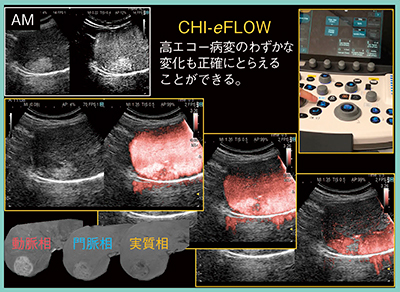

従来,Kupffer相での病変の輝度変化は背景Bモードの影響を受けるため,AM法での評価が望ましいと考えられてきたが,AM法でも判断が難しい症例もある。そこで新たに,背景Bモードの影響を受けることなくKupffer相での輝度変化を評価可能な高音圧ドプラモードCHI-eFLOWがARIETTA 850に搭載された。CHI-eFLOWは,高音圧で造影剤を破壊し疑似ドプラ信号を発生させることで,造影剤を感度良く検出可能となる。操作はわずか2ステップと簡便であり,意図しない造影剤の破壊予防のため,モード遷移後に低音圧のままROIを設定できる。そのため,プローブを体表から離すことなく設定でき,検査を妨げないことも特長である。実際の画像は,輝度変化が非常にわかりやすいものとなっている(図5)。

また,肝血管筋脂肪腫などは,AM法,PI法,Low MI法のいずれもKupffer相にて高エコーとなるが,CHI-eFLOWでは病変内の造影剤の多寡も確認可能となる(図6)。特に,高分化型肝細胞癌の治療適応の判断に有用である。

図6 CHI-eFLOWによる高エコー病変内の造影剤の多寡の評価